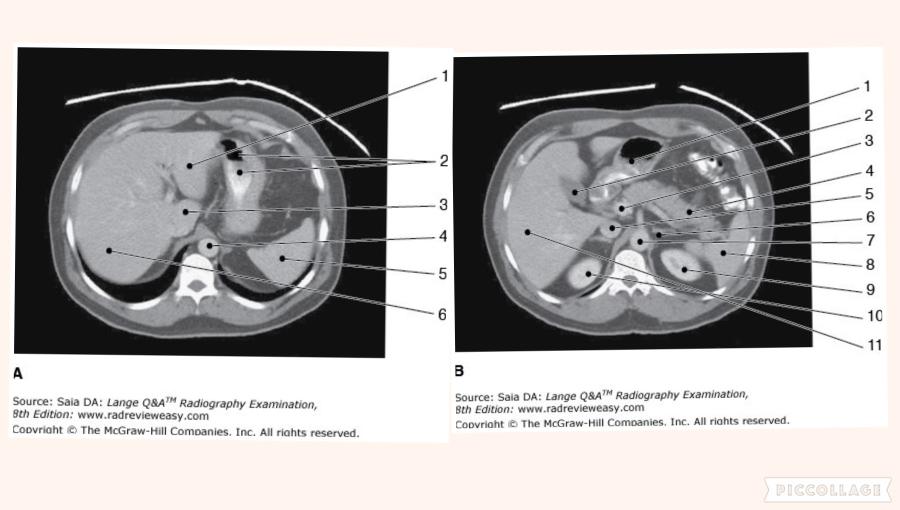

Which of the following is represented by the number 3 in the figure below?

Aorta

The structure labeled number 2 in Figure 6–3, image B is the

gallbladder

Which of the following statements is (are) true with regard to the two CT images seen below?

- Image A illustrates more superior structures.

- The images are sagittal reconstructions.

- The exam was performed without artificial contrast.

1 only